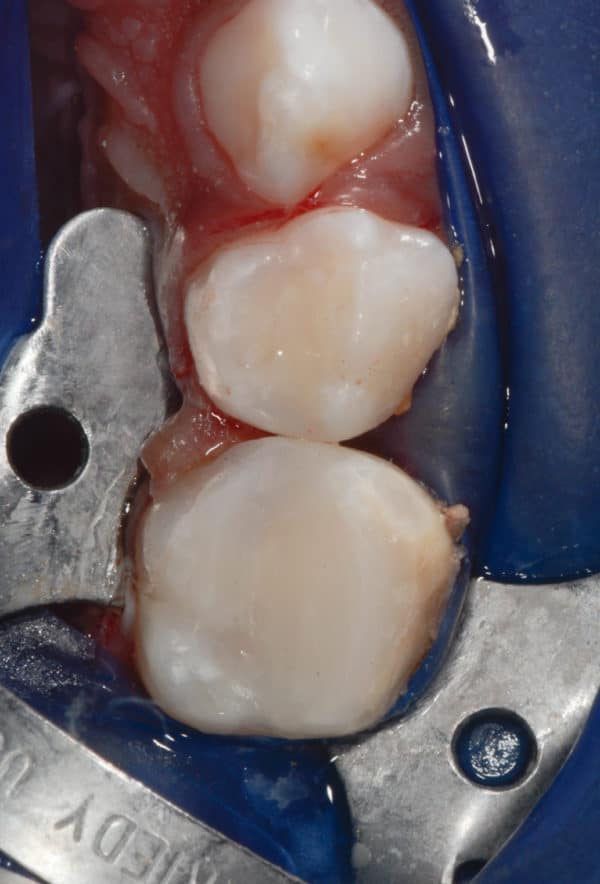

Caries dentaires affectant deux molaires de lait. Un champ d’isolation empêche la contamination des surfaces dentaires traitées, évite les accidents dentaires et réduit le contact de matériels avec la bouche de l’enfant.

Les différentes étapes pour soigner une carie sur une molaire de lait sont illustrées, depuis l’ouverture de la cavité carieuse, le nettoyage du tissu malade et la restauration de la dent avec du composite.